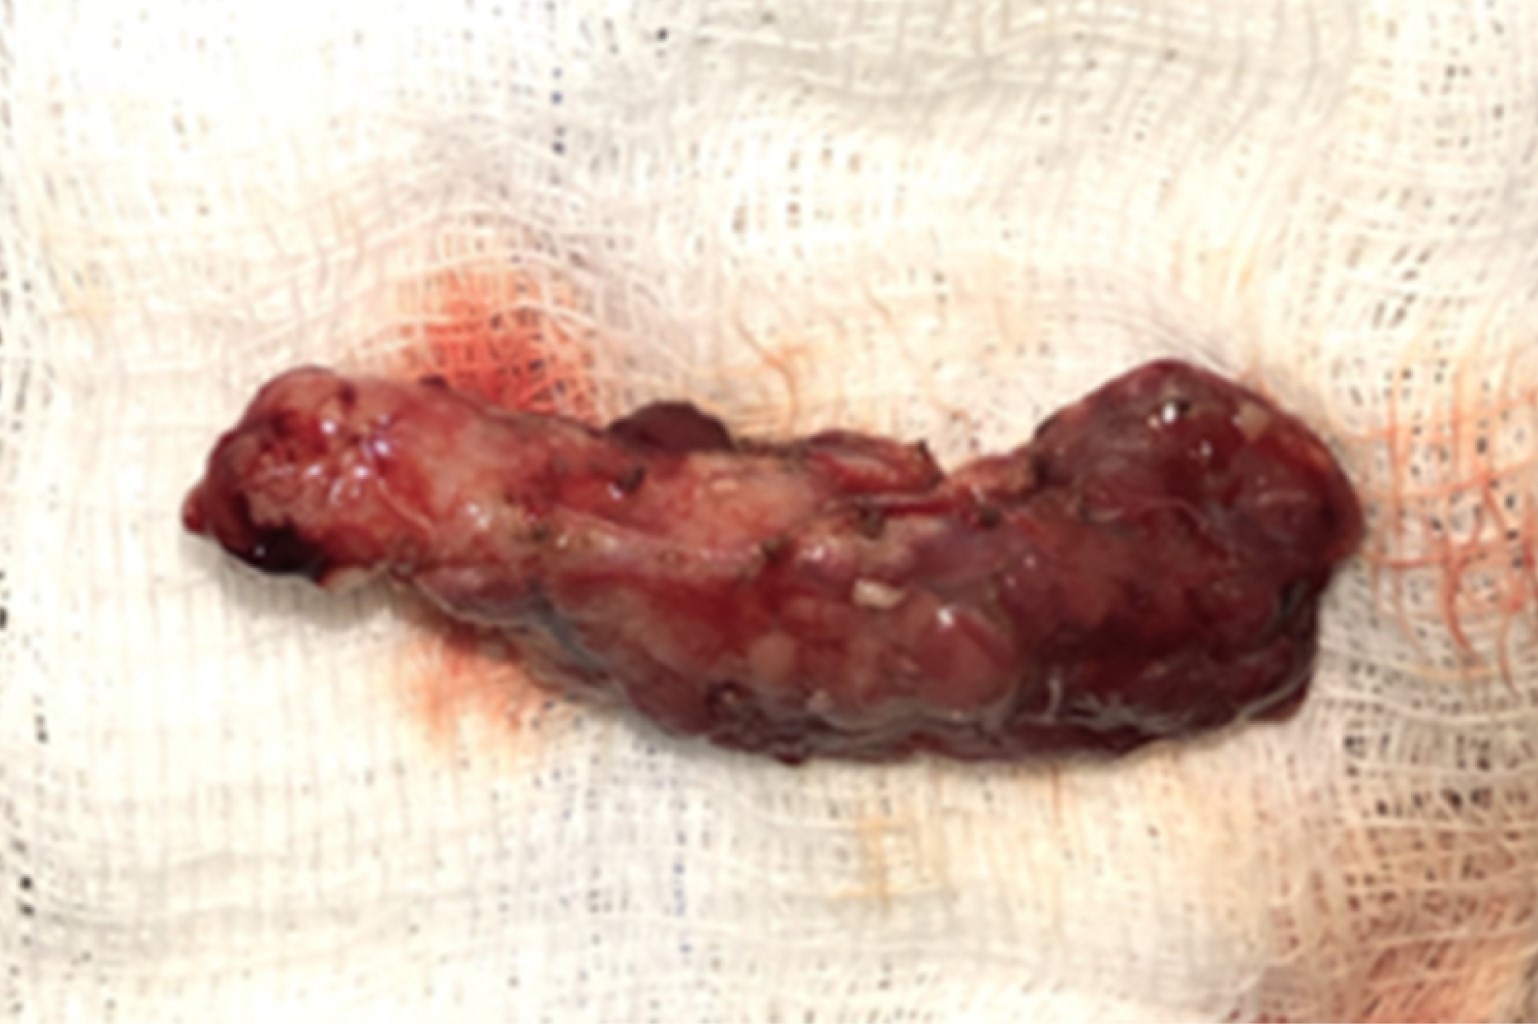

Inicia su padecimiento a las 4 horas de vida con hipoglucemia de 11 mg/dL que amerita aporte de glucosa-kilo-minuto (GKM) de 13-14 mg y al cuarto día de vida presenta crisis convulsiva tónico-clónica generalizada con bradicardia y cianosis. Ingresa al Instituto Nacional de Pediatría referida del Hospital General de Cancún el 7/06/18, se inicia manejo con octreotide de 3.1 μg/kg/dosis cada 6 horas y se le realiza tomografía por emisión de positrones (PET, por sus siglas en inglés) (Figura 2) con probable hiperinsulinismo difuso; se observa evolución tórpida con mala respuesta al tratamiento, por lo que se programa para pancreatectomía (Figura 3).

Figura 3